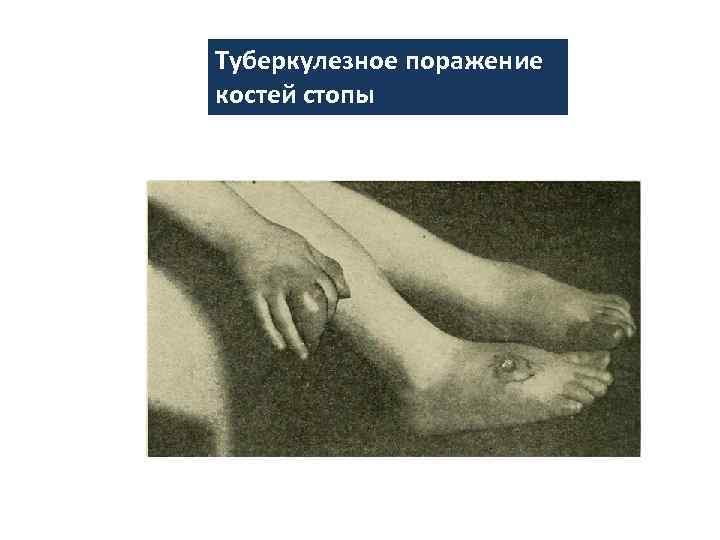

Туберкулезное поражение костей стопы

Туберкулезное поражение костей стопы